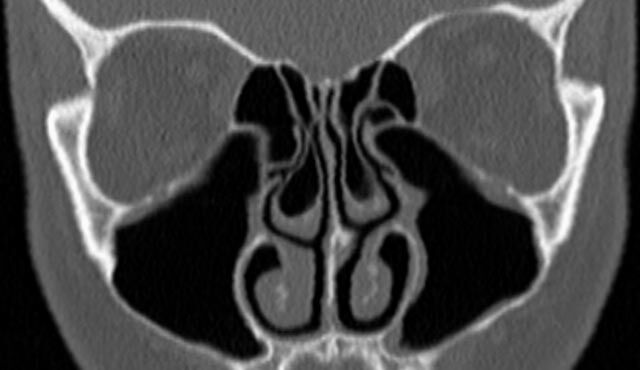

Kopf

• Nasennebenhöhlen (Entzündungen, Tumore)